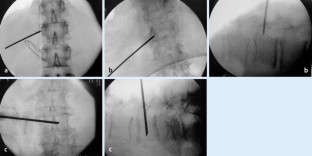

Wir haben in einer prospektiven Studie 92 Wirbelkörper (Th8–L5) bei 60 Patienten im Alter von 76,8 (60–95) Jahren in linksmonopedikulärer Technik über einen para-/transpedikulären Zugang augmentiert und eine Auswertung der Kanülenposition, applizierbaren Zementmenge sowie eine CT-gestützte Analyse der Zementverteilung durchgeführt. Hierzu wurde der Wirbel in der Frontalebene in 9 Segmente unterteilt. Die Kanüle wurde in 85,9% (79/92) im mittleren, in 11,9% (11/92) im rechten und in 2,2% (2/92) im linken Wirbelkörperdrittel platziert. Punktionsassoziierte Komplikationen wurden nicht beobachtet. Das applizierte Zementvolumen lag bei 4,5 (1,5–9,0) ml.

We present a prospective study on 92 vertebral body fractures (Th8–L5) in 60 patients, aged 76.8 (60–95) years, which were treated by unipedicular vertebroplasty using a para-/transpedicular approach. We evaluated needle position, injected cement volume, and cement deposition based on CT scans. The vertebral body was divided into nine segments in a frontal plane view. The needle was placed in the middle third in 85.9% (79/92), in the right in 11.9% (11/92), and in the left third in 2.2% (2/92). Complications associated with cannulation were not observed. The injectable cement volume was 4.5 (1.5–9.0) ml.

Abb. 2